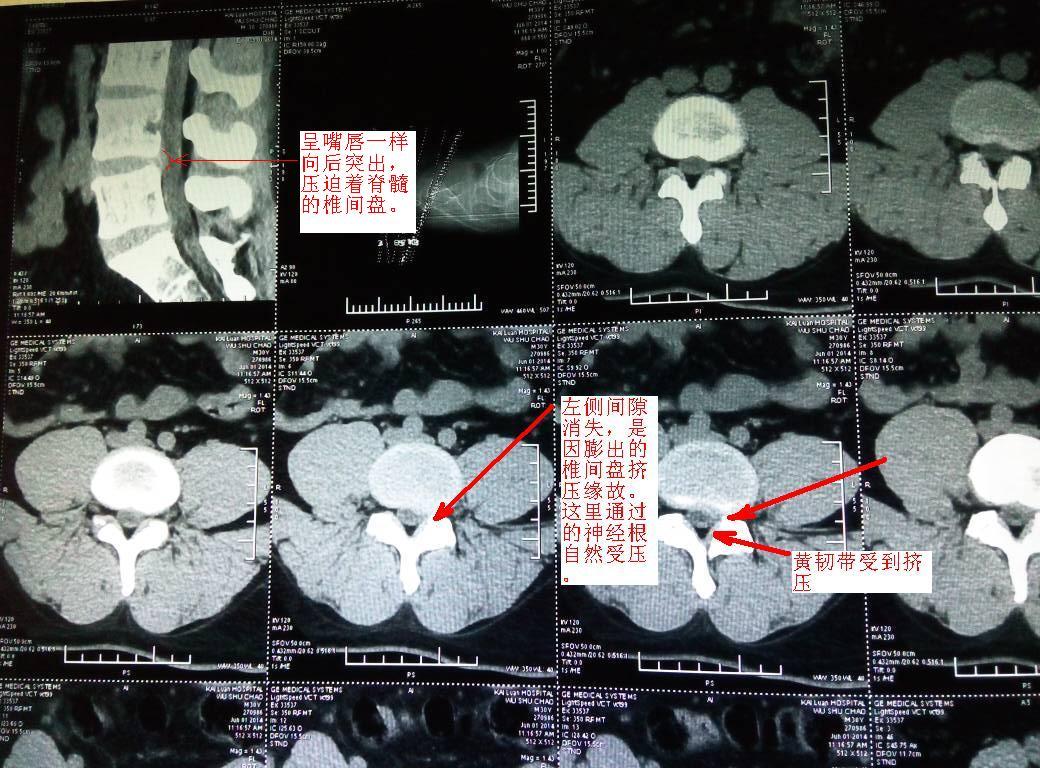

腰椎间盘突出,l5和骶骨峡部不连,左侧骶髂骨错缝!

图片尺寸2560x1920